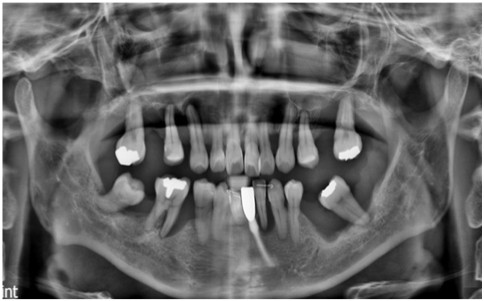

먼저 구강 내를

확인해 보았더니

다수 치아의 상실로 인해

치아의 배열이 흐트러져 있고,

잔존 치아들도

동요도가 심한 상태였는데요.

정밀한 검사를 위해

파노라마 사진을

촬영해 보았더니

만성 치주염으로 인해

다수 치아 상실과

심각한 골소실이 보였으며

이로 인해 양측 어금니 부위의

교합 및 수직 고경이 소실된 상태였습니다.

환자분께서는 2년 반쯤에

내원해 주셨던 적이 있으셨는데요.

위 사진은

그 당시 파노라마 사진으로

그때도 만성 치주염 진단을 받으셨지만

지속적인 치료와

관리가 잘되지 않아

현재 더 심해진 상태입니다.